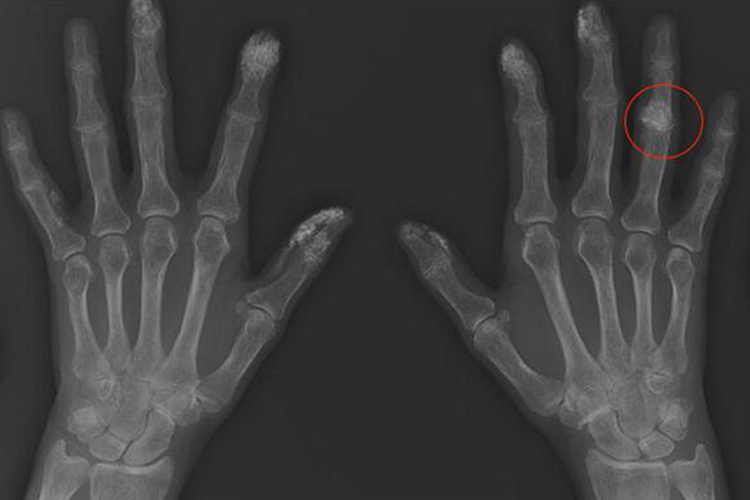

手指关节由骨骼与纤维结缔组织、软骨等构成,手指关节钙化可导致手指灵活度下降,影像学检查可见钙化灶。

手指关节由骨骼、软骨、韧带、肌肉等组织构成,手指关节钙化可表现为关节的灵活度下降,手指僵硬,严重时可伴随疼痛,影像学检查可见病损部位有不同形态的高密度的钙化影。